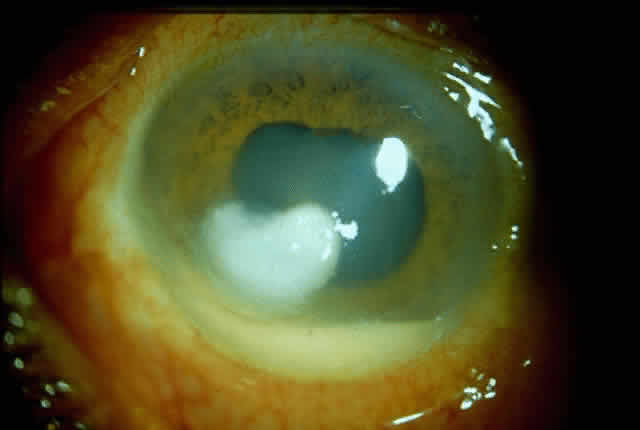

Bacterial corneal infections are caused by a wide variety of organisms. Pneumococcus seems to be the most common causative organism (Fig. 2); however, staphylococcal, pseudomonal, and gonococcal infections frequently are encountered.3 This may be related to chronic dacryocystitis.5

|